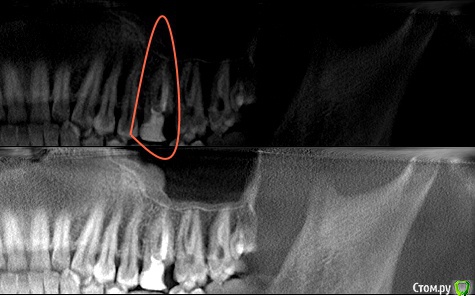

cicamox Опубликовано 29 августа, 2020 Поделиться Опубликовано 29 августа, 2020 Подскажите, возможно ли лечение, выделенного зубa? Ссылка на комментарий

АнтонТЛТ Опубликовано 29 августа, 2020 Поделиться Опубликовано 29 августа, 2020 Пограничная ситуация, можно определить только при очном осмотре. Ссылка на комментарий